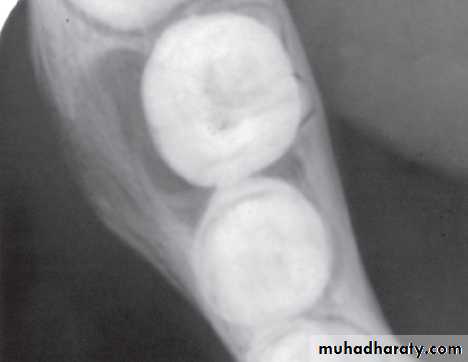

• Detect secondary cariesPosterior bite wing Radiograph

Record the width of spaces created by prematureloss of deciduous teeth

Indications of bite wing radiograph

(A) Interproximal caries detection;

(B) Evaluate the interdental bone